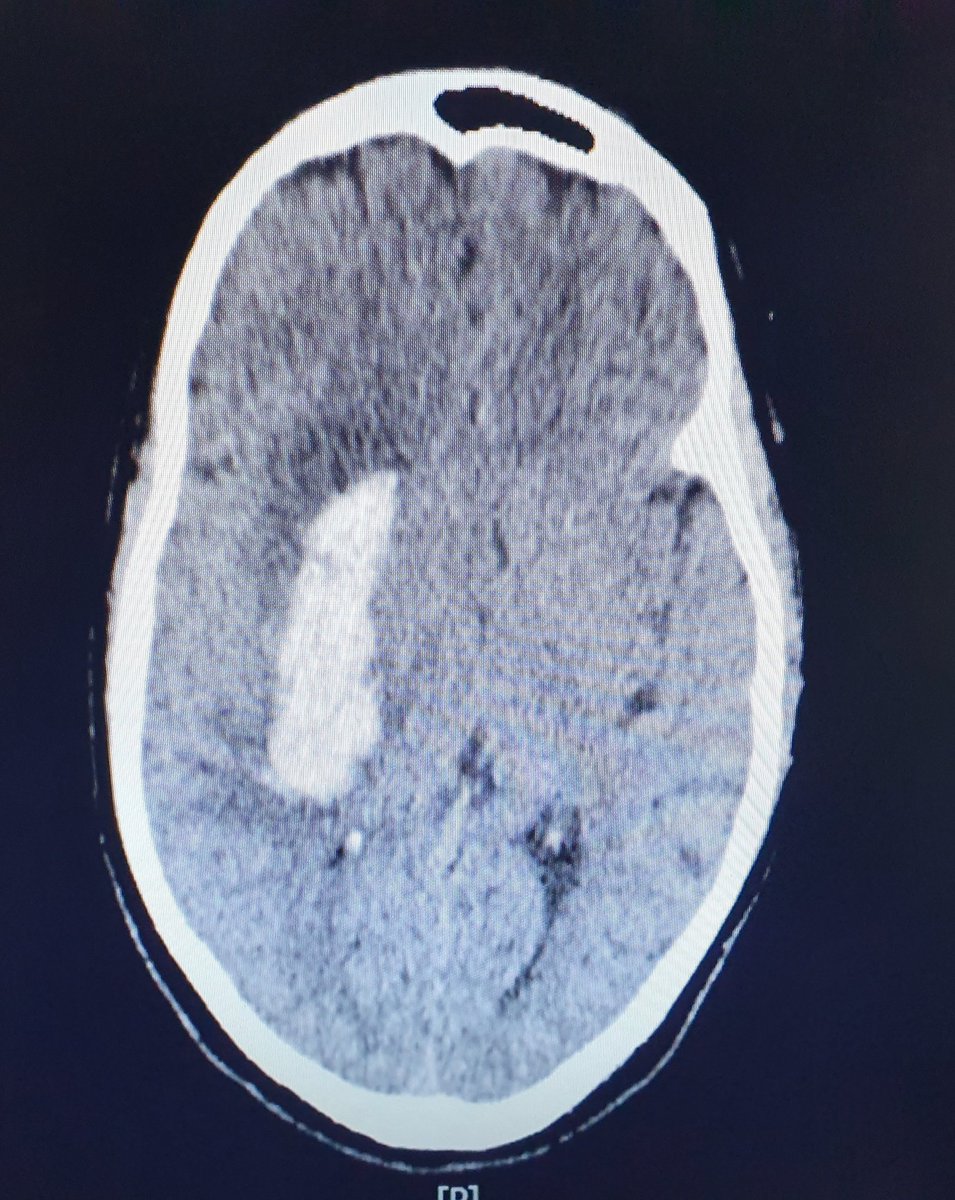

CT Brain tu tunjuk yang dah berlaku pendarahan dalam otak sebab tekanan darah yang terlalu tinggi.

Salur darah dah pecah.